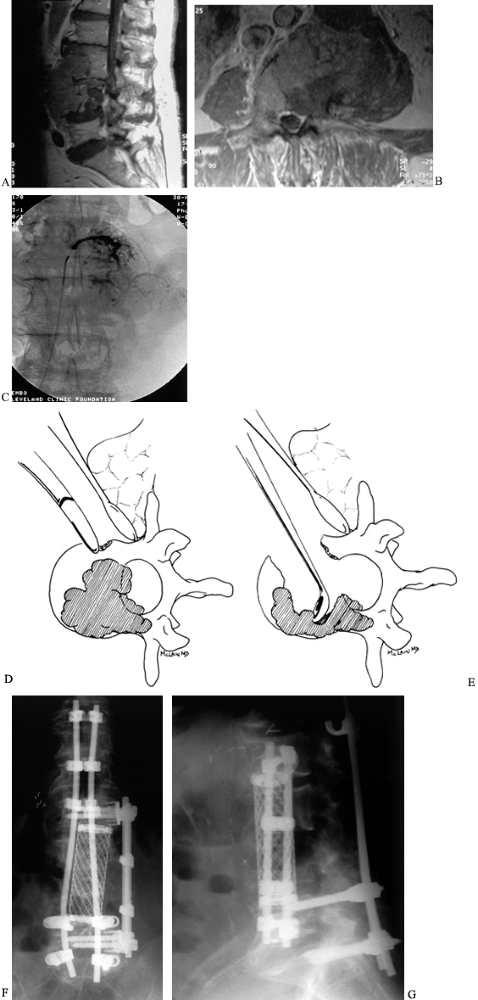

radiotherapy (Fig. 152.4). Follow-up with MRI and serum protein electrophoresis provides the earliest indication of recurrence or dissemination.

![]() |

|

Figure 152.4. A: AP radiograph of a 68-year-old woman with solitary plasmacytoma of the T-12 vertebra, refractory to radiotherapy. B: MRI shows the extent of the tumor. C:

Complete anterior/posterior excision was followed by anterior tricortical graft and long segmental instrumentation posteriorly. She was disease free for 5 years before recurrence and dissemination occurred. |